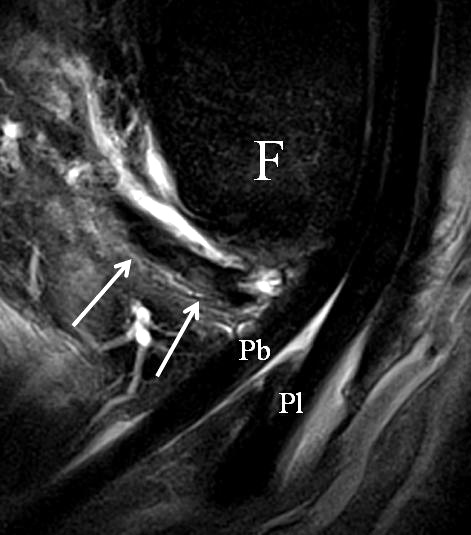

Der Ursprung des Ligamentum fibulocalcaneare liegt unmittelbar kaudal und dorsal des Ursprungs des Ligamentum fibulotalare anterius, so dass gehäuft kombinierte Verletzungen und auch ein gemeinsamer knöcherner Ausriss beobachtet werden. Nach kaudal dorsal verläuft das Band dann nach medial konvex unter die Peroneussehnen. Danach ist ein schräg deszendierender, gestreckter Verlauf bis zum calcanearen Ansatz abgrenzbar (Abb. 10). Dieser zu allen drei Standardebenen schräge Verlauf erschwert häufig die Diagnostik des LFC vor allem bei subtileren Verletzungen. Spezialprojektionen, die dem Bandverlauf orthograd folgen (entweder schräg coronar oder schräg sagittal) erleichtern auch hier die Diagnostik (Abb. 11) insbesondere nicht dislozierter Avulsionen. Assoziierte Verletzungen der Peroneussehnenloge müssen mit beurteilt werden, wobei neben Verletzungen der Sehnen und Sehnenscheiden die Beurteilung des Retinaculum peroneum superius und inferius wichtig ist. In einem Kollektiv von Patienten mit chronischen Außenbandinstabilitäten weisen 50% der Patienten eine Verletzung dieser Strukturen auf 5. Auch hier erleichtern hochauflösende Techniken die Diagnostik (Abb. 12).